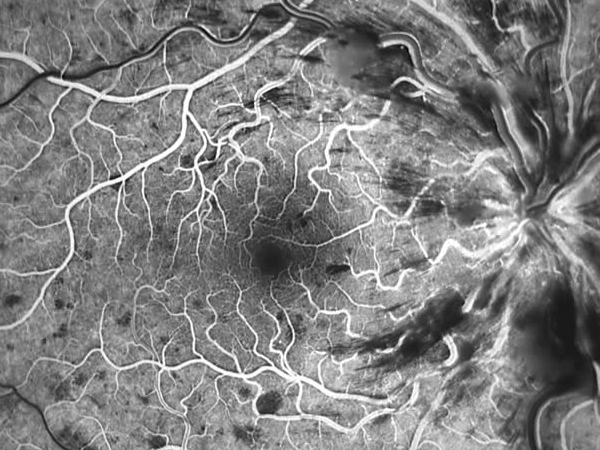

Fluorangiografia retinica

La fluorangiografia è un esame fondamentale per lo studio della retina. Si esegue iniettando in vena un colorante fluorescente e scattando poi delle foto con uno strumento specifico.

Nella forma ischemica è essenziale per monitorare l'estensione dell'ischemia e impostare un eventuale trattamento laser.